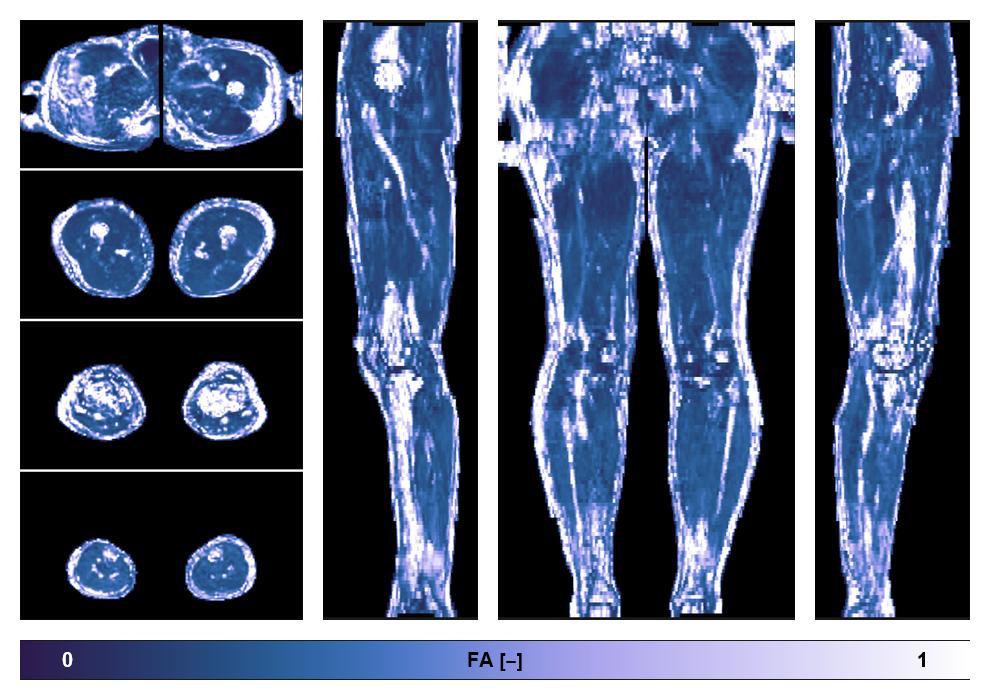

• Fractional anisotropy

IVIM corrected whole leg muscle fractional anisotropy obtained from diffusion tensor imaging.